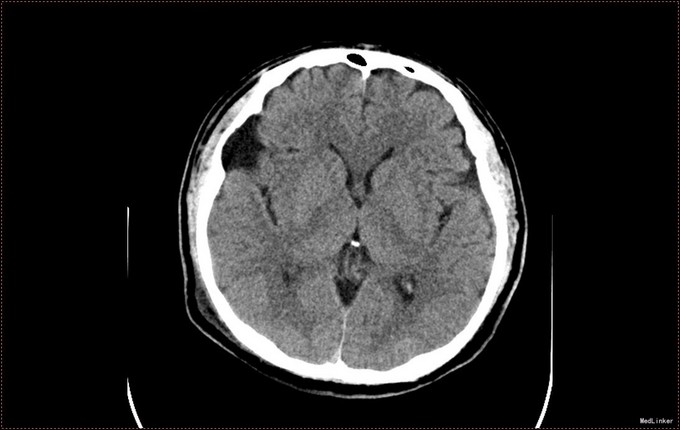

患者,男,53岁。以“左侧肢体疼痛伴无力1周”为主诉入院。患者1周前无明显诱因出现左侧肢体无力,伴酸痛,头部闷胀感,症状持续不缓解,于我院就诊,行头部CT及MR提示右侧顶枕叶硬膜下血肿。右侧额颞叶蛛网膜囊肿。患者为求进一步治疗,急诊以“硬膜下血肿”为诊断,收入病房。患者病来精神状态差,饮食睡眠可,二便可,体重无明显变化。否认近期头部外伤史。

入院查体:T:36.5℃ ,P:68次/分 ,BP:130/80mmHg , R:16次/分。步入病房,自主体位。神清语明,问答准确,查体合作,精神状态良好,定向力完整。粗测视野正常,双侧瞳孔等大正圆,D≈3.0mm,双侧眼球活动自如,对光反射灵敏。四肢活动自如,左侧肢体肌力V-级,右侧肢体肌力Ⅴ级,肌张力正常。深浅感觉检查未见异常。头CT及MR提示右侧颞极蛛网膜囊肿,右侧亚急性硬膜下血肿

患者诊断明确,完善术前检查行局麻右侧钻孔冲洗引流术,予常规治疗。术后3天拔管,复查头CT硬膜下血肿消失,但脑组织膨胀不良。患者左侧肢体肌力恢复正常,无头晕头沉症状,顺利出院。